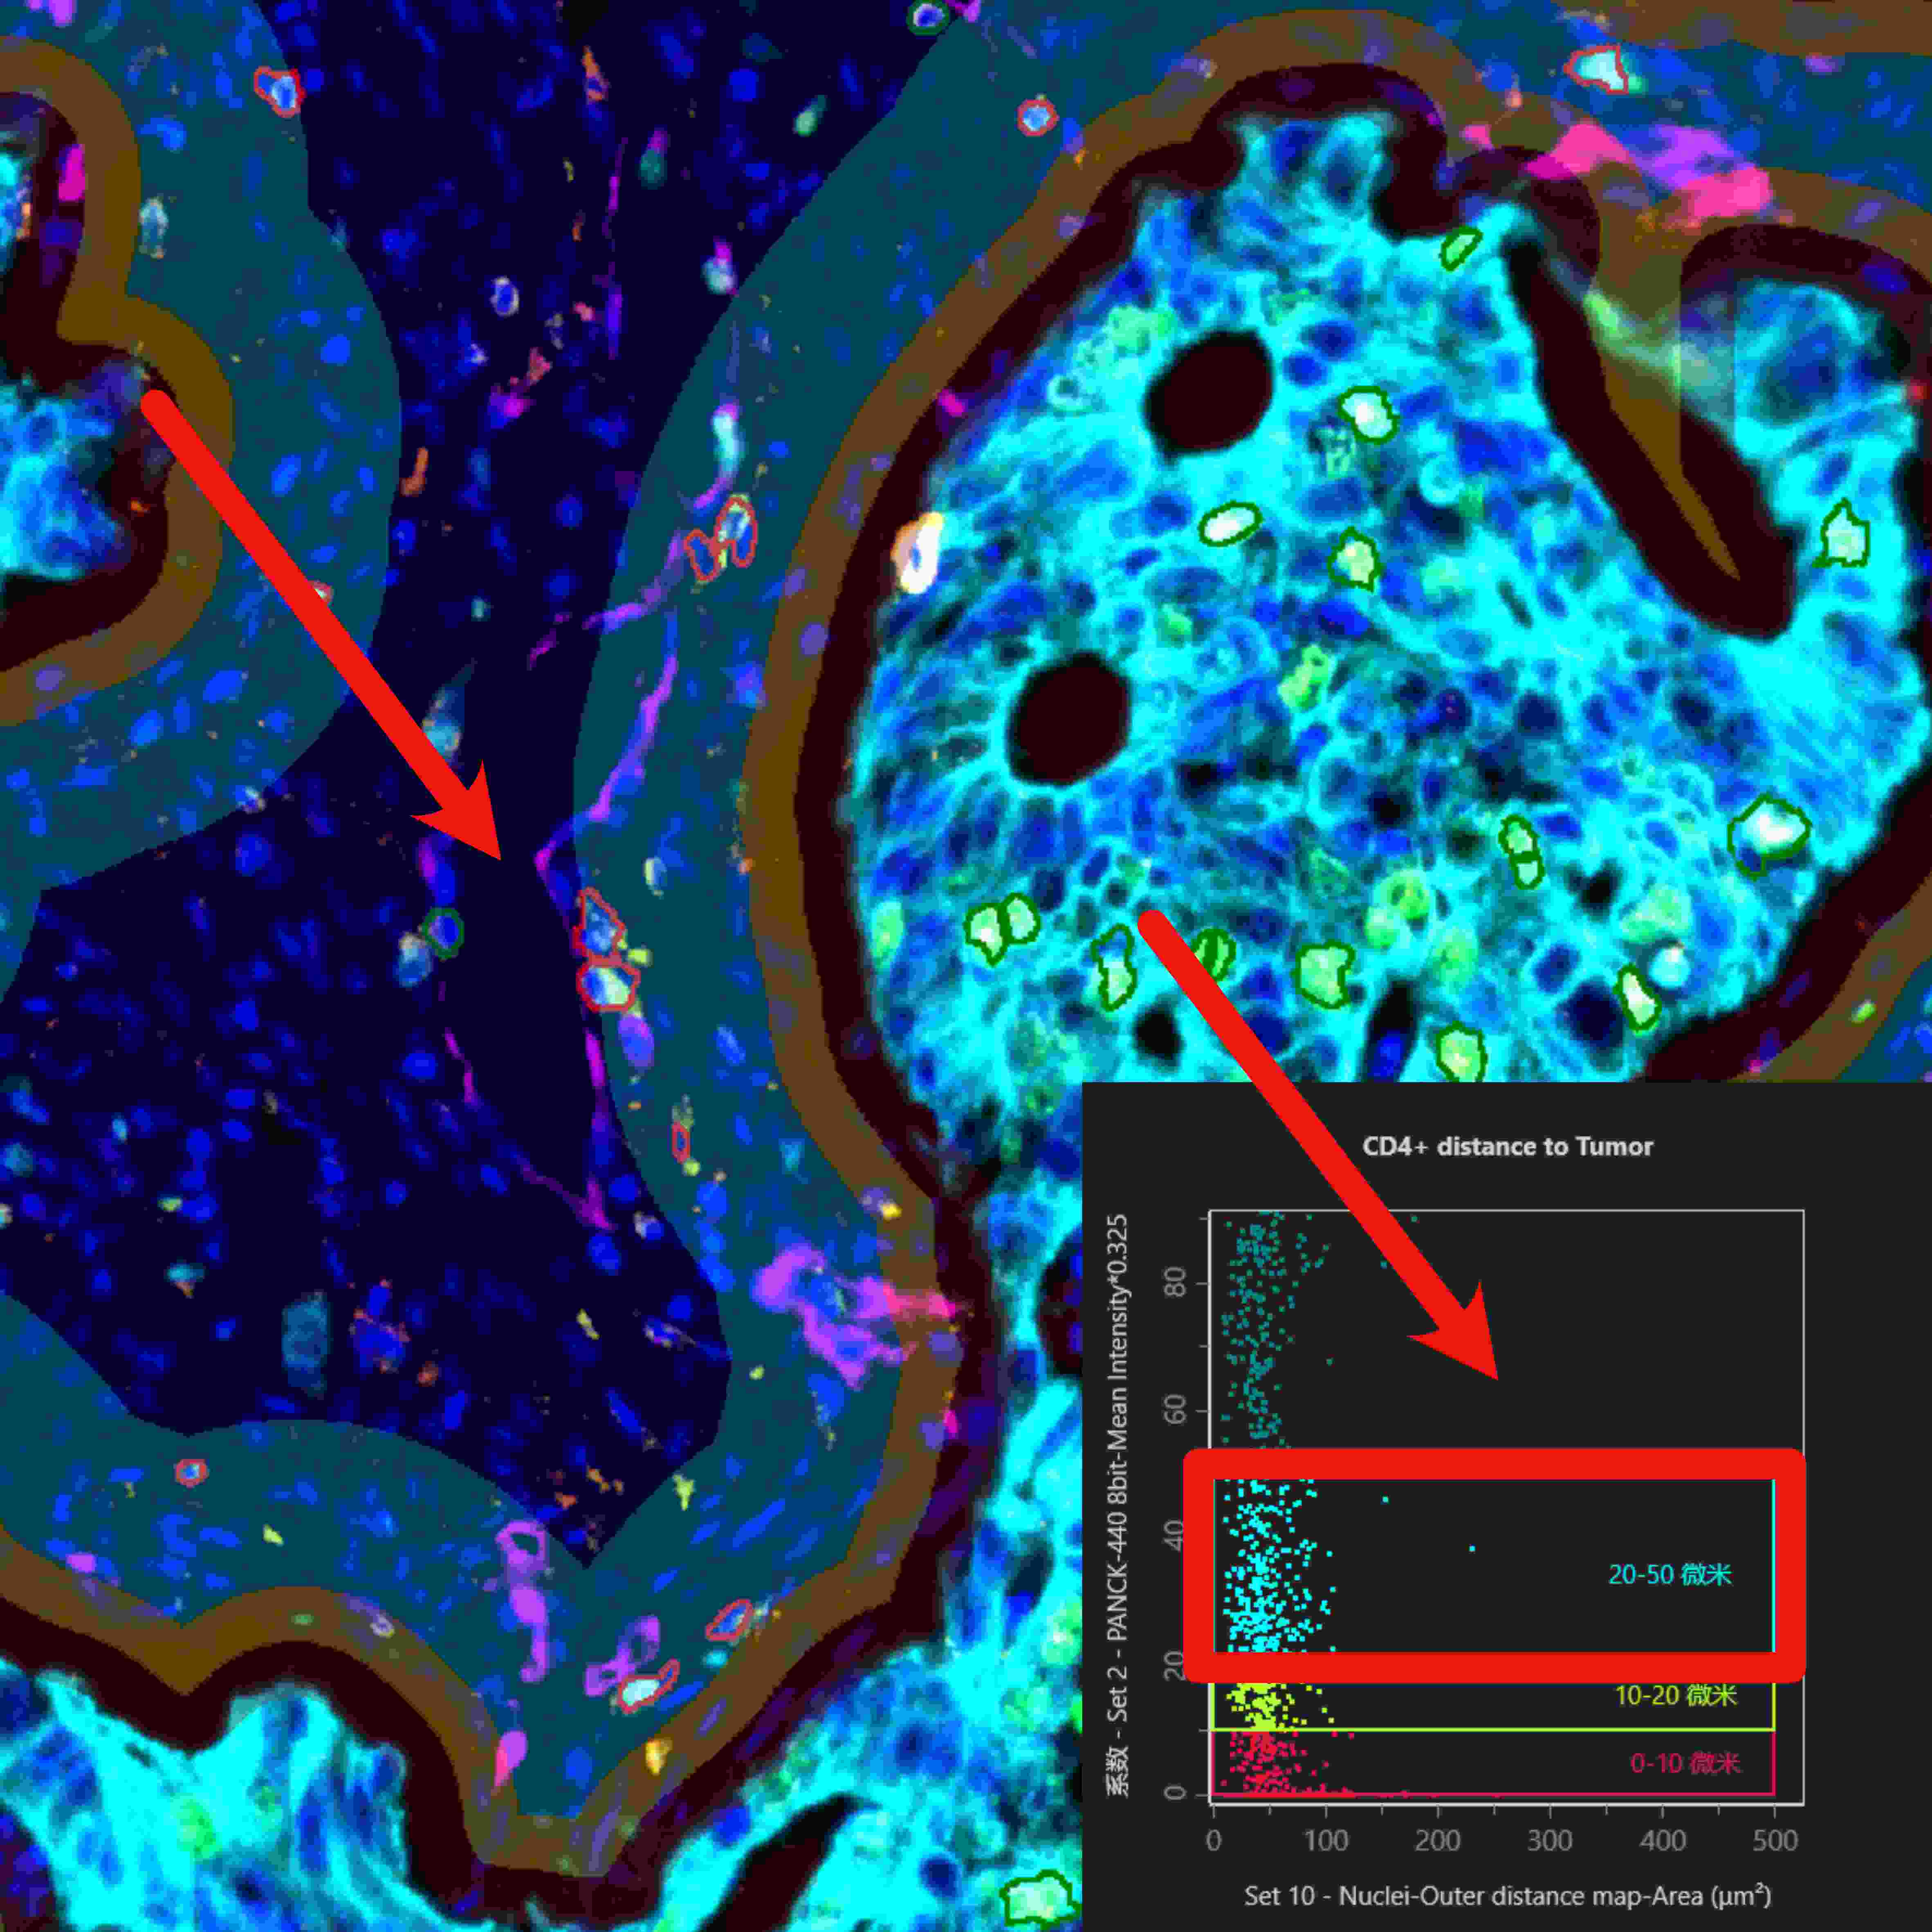

在单细胞表型分析与组织识别分析的基础上,利用StrataQuest可进一步分析不同细胞与不同组织类型间的空间分析关系。

除上述一站式完整解决方案外,TissueGnostics 还能助力研究人员开展更深入的实验方法研究,通过定制化染色扫描分析服务获取更丰富的分析数据。例如,在组织切片染色扫描环节,可依据实验方案实现 50 种以上荧光标记的多轮循环染色扫描;后续分析中,还能生成空间水平的细胞间连线图、组织周围特定距离细胞分布图等多元化结果。